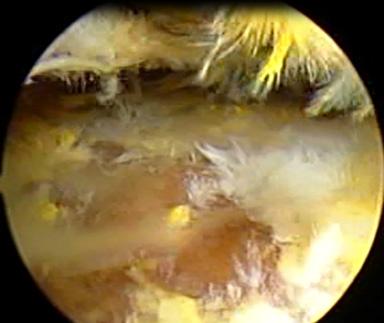

Manejo ortopédico de la artropatía hemofílica en México. Por: Dr. Armando R. Hernández Salgado, Ortopedista y Traumatólogo, Cirujano de Artroscopia y Cirugía de Rodilla, Especialista en Artropatía Hemofílica, Asesor Voluntario de FHRM. Pág. 109